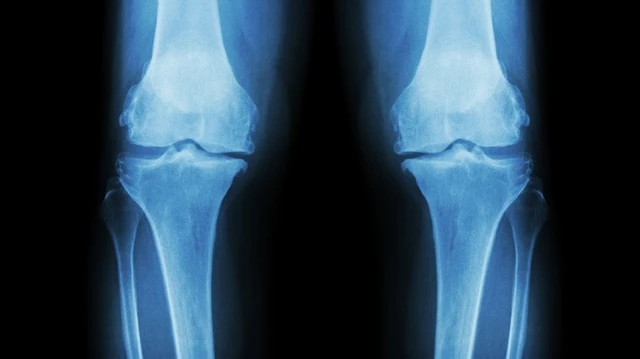

Bạn có từng cảm thấy đau nhức khớp gối sau khi vận động mạnh? Đó có thể là triệu chứng của tổn thương sụn khớp. Vậy làm thế nào để khắc phục? Ghép sụn khớp có phải là giải pháp tốt nhất?

Bất kỳ hoạt động nào của cơ thể cũng có sự tham gia và phối hợp từ nhiều xương khớp khác nhau. Hầu hết, chúng ta thường không cảm nhận được sự ma sát hay cảm giác đau đớn là bởi sự bảo vệ từ sụn khớp. Vậy những điều cần biết về sụn và nguyên nhân gây tổn thương sụn thường gặp là gì, chúng ta hãy cùng tìm hiểu thông qua bài viết dưới đây.

Sụn xương là một loại mô liên kết mềm dẻo tham gia vào cấu trúc của bộ xương và được tìm thấy ở nhiều nơi trong cơ thể người. Sụn xương đóng vai trò như một lớp đệm trong các khớp, nó hoạt động tương tự như một bộ phận giảm xóc, bảo vệ và giúp giảm chấn động, ngăn chặn sự cọ xát giữa hai đầu xương khi di chuyển. Cùng tìm hiểu cụ thể hơn sụn xương có tác dụng gì qua nội dung sau đây.